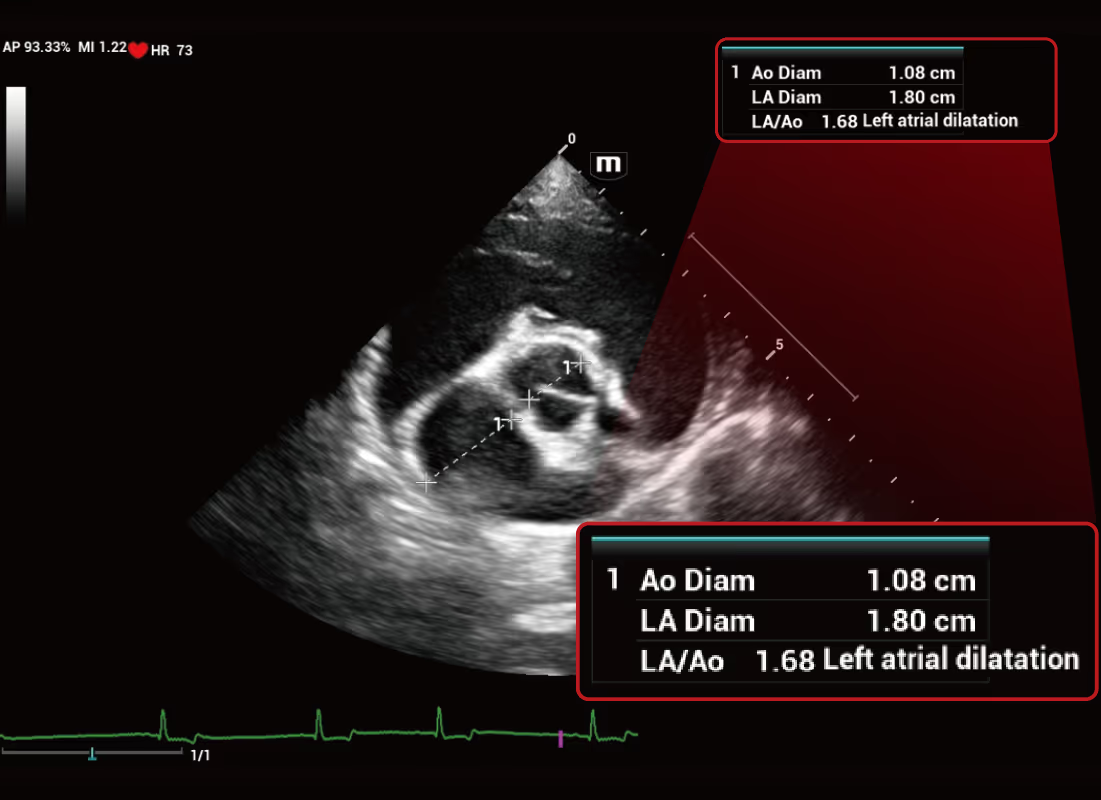

iMeasure, olası veya şüphelenilen klinik durumları anında ekranda önerir.